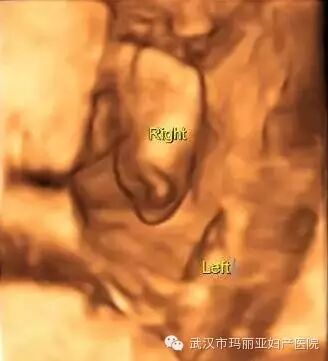

武汉玛丽亚妇产医院引进的世界领先的美国GE-E8四维彩超设备室目前世界上最先进、分辨率最高的彩色超声设备,具有即时立体成像、清晰准确的特点。

它能够多方位、多角度地观察宫内胎儿的生长发育情况,为早期诊断胎儿先天性体表畸形和发育异常提供科学依据。还能对胎儿的体表进行检查,如唇裂、脊柱裂、大脑、肾、 骨骼发育不良等,以便尽早的进行治疗。

玛丽亚美国GE-E8四维彩超排畸成功案例

案例一:三个脚趾半个脚掌